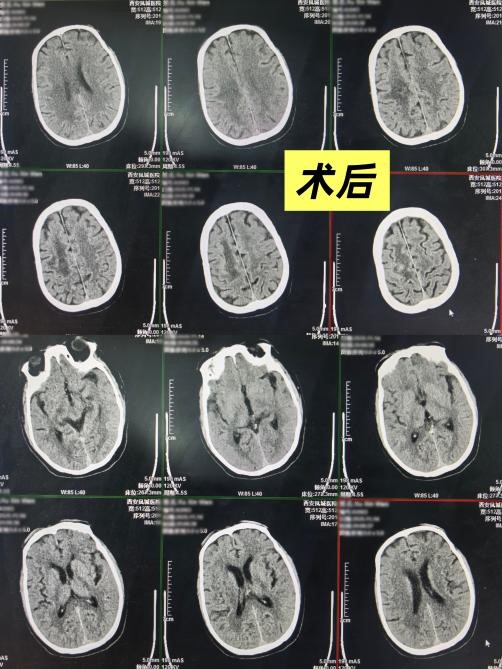

术后,患者意识逐渐恢复清楚,能够积极配合治疗,更令人欣喜的是,其左侧肢体的肌力得到了改善,左侧上肢恢复至3级,下肢恢复至2级。这一系列积极的转变,凝聚了裴宾宾医生及科室医护团队精湛的医术、高度的责任心以及对生命的无限珍视。他们不仅挽救了患者的生命,更最大限度地守护了其未来的生活质量,用实际行动践行了“生命至上”的庄严承诺。